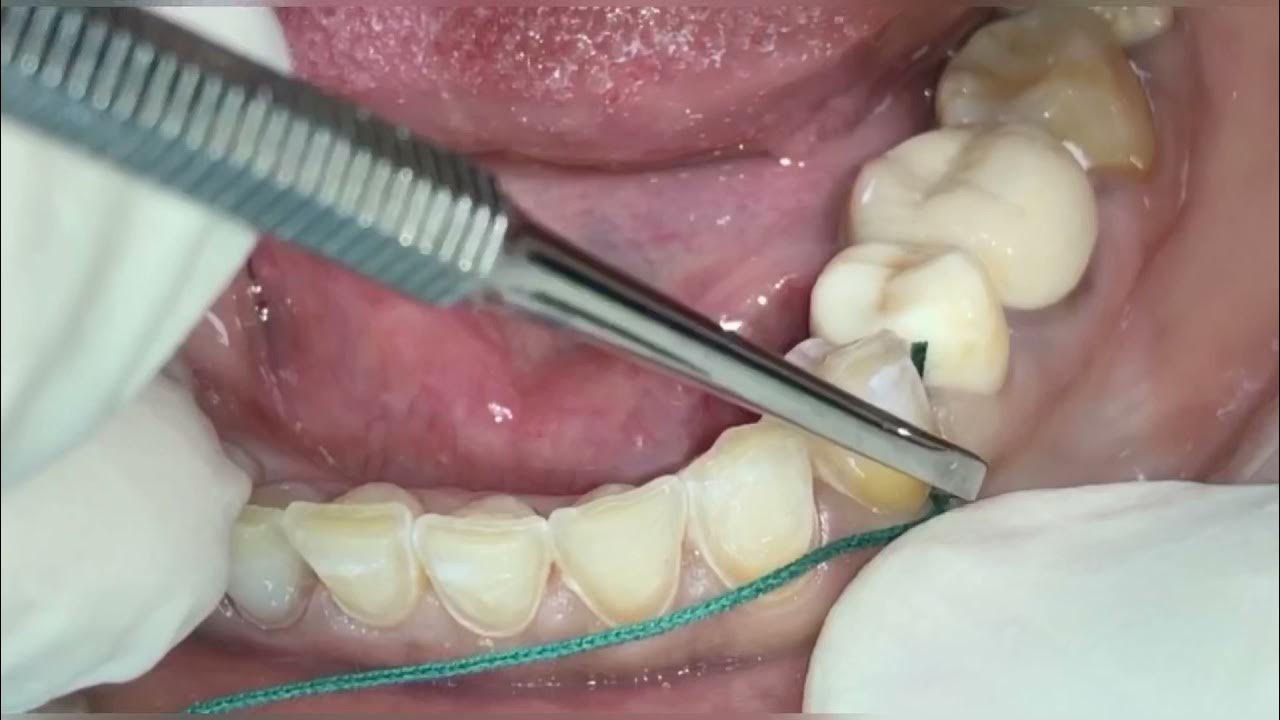

Double Cord Technique In Gingival Retraction . The double cord technique involves placing a small diameter cord in the gingival sulcus first, leaving it in place, and then packing a larger diameter cord over the first. (figs 1, 2 & 3) gingival sulcus. The moisture in the gingival sulcus is absorbed by these retraction cords while gingival tissue is displaced mechanically,. The gingival retraction cord technique can be done with a single cord or a double retraction cord. To measure and compare the amount of gingival displacement, time taken for retraction and haemorrhage control produced by single. Often, a dentist can pull out the second cord (which would be closer to the margin and. This gingival cord retraction technique allows for more significant retraction of the gums.